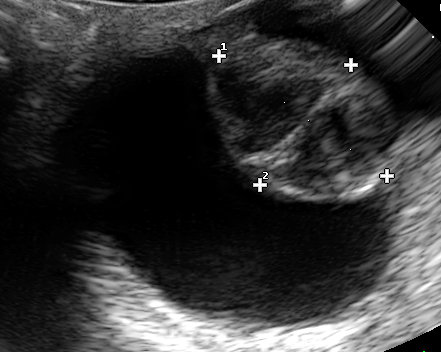

Fig 1 and 2: Mature diabetic cataract showing a swollen lens and clear water clefts forming and an ultrasonograph of a similar lens.

Diabetic Cataracts in Dogs – The problem: Lens capsule rupture

Group 1 cases are thought to have higher levels of AR in their lenses and can become genuine emergency

cases. The lens can swell so dramatically that the lens capsule ruptures which in turn leads to a severe uveitis and risks the blinding secondary consequences of retinal detachment and eventual glaucoma.